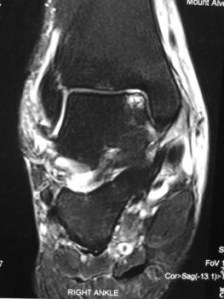

MRI scan showed an osteochondral lesion involving the superomedial aspect of the talar dome.

This diagnosis would have been missed if not for a high index of suspicion and by the use of an MRI scan.